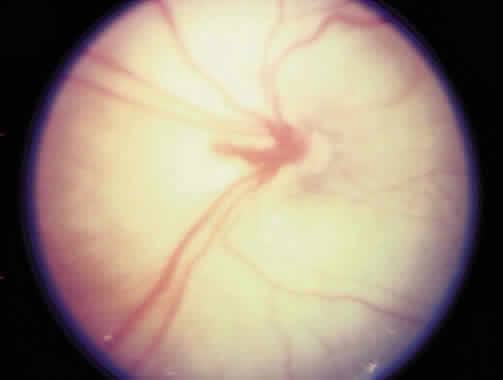

To define location, the retina was divided into three zones with the optic nerve as the center, since retinal vascular growth proceeds from the disc toward the ora serrata (Fig. 2). Zone I consists of a circle, the radius of which extends from the disc to twice the distance from the disc to the center of the macula (twice the disc-fovea distance in all directions from the optic disc). Zone II extends from the edge of zone I peripherally to a point tangential to the nasal ora serrata and around to an area near the temporal anatomic equator. Zone III is the residual temporal crescent of retina anterior to zone II. This is the zone that is vascularized last in the premature eye, and it is the zone most frequently involved with ROP. The extent of disease is specified as hours of the clock (see Fig. 2). The second parameter specified in the 1984 classification is staging of the disease, that is, the degree of abnormal vascular response observed. Four stages were recognized, and staging for the eye as a whole receives the stage of the most severe manifestation of ROP present. Stage 1 (demarcation line) is defined as a thin but definite structure that separates avascular retina anteriorly from the vascularized retina posteriorly. Abnormal branching or arcading vessels are seen leading up to the line. It is flat and white and is in the plane of the retina. Stage 2 (ridge) is present when the line of stage 1 has grown, has height and width, and occupies a volume extending up out of the plane of the retina. The ridge may be pink or white, and vessels may leave the plane of the retina to enter it. Small tufts of new vessels may be seen on the surface of the retina posterior to the ridge. These vessels do not constitute fibrovascular growth, which is a necessary condition for stage 3 ROP. Stage 3 (ridge with extraretinal fibrovascular proliferation) exists when extraretinal fibrovascular proliferation is added to the ridge of stage 2 ROP (Fig. 3). Stage 3 is arbitrarily further subdivided into mild, moderate, and severe. Stage 4 (retinal detachment) is the addition of retinal detachment to stage 3 findings. Traction or exudation cause the retinal detachment. Progressive vascular incompetence, occurring with the changes at the edge of the abnormally developing retinal vasculature, is noted by increasing dilation and tortuosity of the peripheral retinal vessels, iris vascular engorgement, pupillary rigidity, and vitreous haze. When the vascular changes are so marked that the posterior veins are enlarged and the arterioles are tortuous, a plus sign is added to the ROP stage number (Fig. 4). Subsequent to the initial ICROP report, completion of the classification of ROP led to the publication of the classification of retinal detachment.41 Stage 4 was expanded to stage 4A and 4B. Stage 4A (Fig. 5) represents extrafoveal retinal detachment, which is a concave traction type of retinal detachment in the periphery without involvement of the macula. These detachments generally are located in anterior zone II or III. Stage 4B (Fig. 6) is a partial retinal detachment including the fovea, which usually extends in the form of a fold from the disc through zone I to involve zones II and III. Stage 5 retinal detachments are total and always funnel shaped. Stage 5 is subdivided based on the shape of the funnel. The funnel is divided into anterior and posterior parts, allowing for four subdivisions, depending on whether the funnel is open or narrow in both parts of the funnel. Although regression was not part of the classification, the committee recognizes that it is the most common outcome of ROP. The various patterns of regression were believed to be too numerous to classify; they are listed in (Table 1).